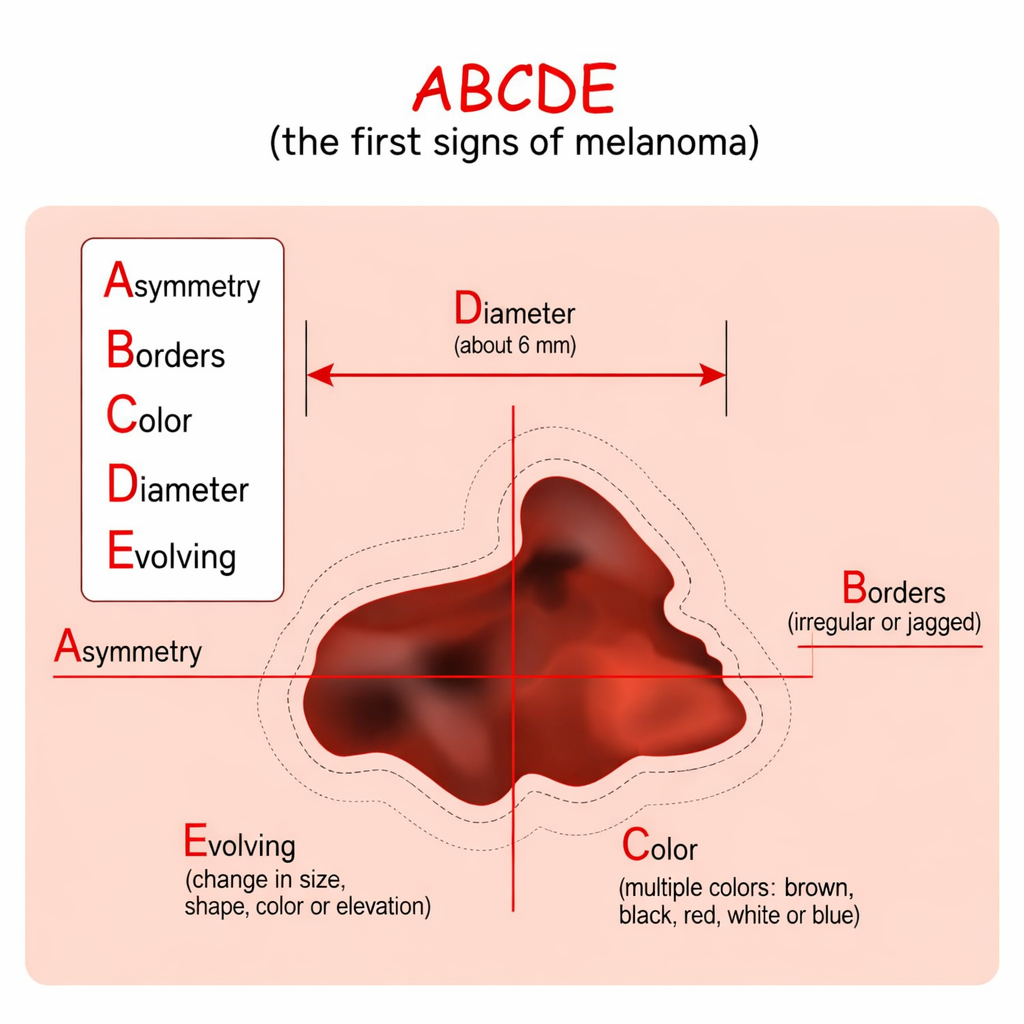

Changes in the skin are also symptoms that are associated with certain forms of cancer. These include jaundice, darkening of the skin, redness, itching, and unusual growths such as unusual moles or changes in the existing ones. Sores that do not heal are also symptoms of certain forms of cancer. This is usually because the cells are supposed to heal themselves, but the unusual cells cause them not to heal. Unusual bleeding or discharge is also a common symptom in all forms of cancer. This includes blood in the urine or stool, coughing up blood, unusual vaginal bleeding, or discharge from the nipple.

In addition, changes in the appearance of the skin, including the development of moles, changes in existing moles, as well as unusual sores, can manifest cancer. In addition, unusual digestive problems, such as difficulty swallowing, indigestion, as well as changes in bowel and bladder habits, can manifest cancer of the digestive and urinary systems.